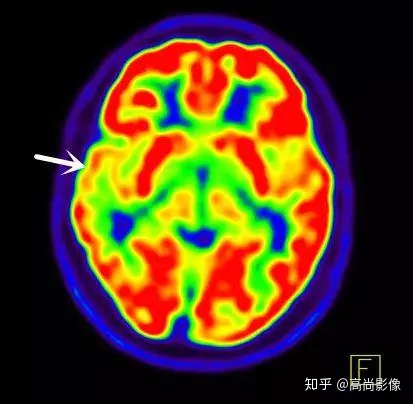

局部18F-FDG代謝顯像主要應(yīng)用于無創(chuàng)定位癲癇病灶。

在國際上,18F-FDG代謝顯像是無創(chuàng)定位癲癇病灶的標準。

發(fā)作間期癲癇灶呈代謝減低

發(fā)作期癲癇灶呈代謝增高